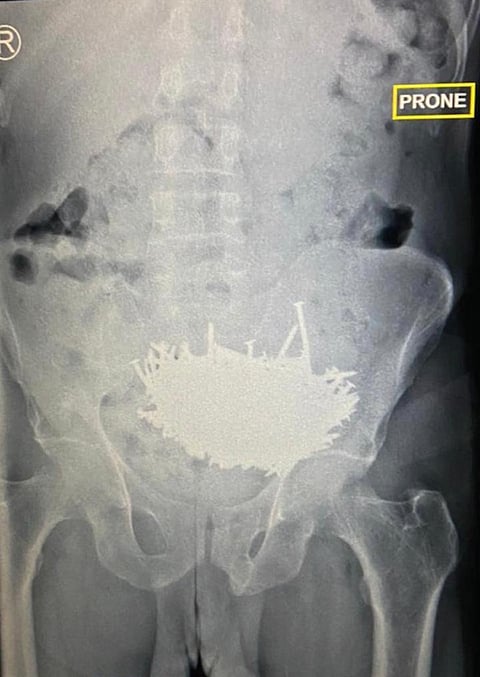

أسهَمَ -بفضل الله- فريق طبي في مستشفى شرق جدة مكون من استشاريين وأخصائيين من قسم الجراحة والتخدير، في إنقاذ حياة مريض نفسي؛ حيث تَمَكّن الفريق الطبي من استخراج عدد 230 مسمارًا وقطعًا من الزجاج من بطنه؛ حيث كان يعاني من آلام وانتفاخ في البطن، وقد أظهرت الفحوصات الإكلينيكية والإشعاعية وجود عدد كبير من المسامير (داخل معدة المريض)، وهو ما استدعى إجراء عملية جراحية طارئة لاستخراج تلك المسامير وقطع الزجاج تحت تخدير عام عن طريق شق جراحي.

وأوضح الفريق الطبي أن حالة المريض مستقرة ولله الحمد، وهو حاليًّا تحت العلاج النفسي ومنوم في غرفة خاصة للمرضى النفسيين.